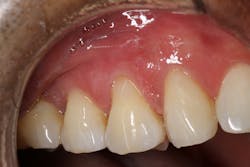

The composite material will appear too white or high in value at first, but after light curing, the composite blends into the color of the natural teeth. A thin interproximal carver was used to carefully seal the gingival margins of the restorations and follow the contour of the natural tooth. This process is made easier by the handling properties of the composite material, which stays in place and doesn’t slump. The material was thoroughly light cured on all three restorations (figure 3).